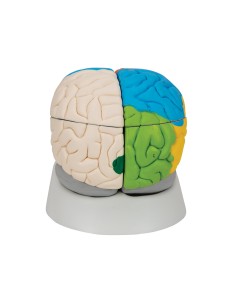

Dal cranio in 22 parti con incastri magnetici ai modelli di colonna vertebrale, da quelli di articolazioni a quelli di cuore, ogni pezzo della nostra collezione è progettato per un’immersione totale nello studio dell’anatomia umana. I nostri modelli, realizzati tramite scansioni di ossa vere, garantiscono un’esperienza tattile autentica e una fedeltà di peso quasi identica agli originali.

Essenziali per studenti e professionisti, i nostri modelli anatomici sono strumenti didattici che permettono di osservare le strutture anatomiche con precisione, eliminando la necessità di dissezioni o studi invasivi. Sono inoltre utili per spiegare ai pazienti le patologie, rendendo la comunicazione più efficace e risparmiando tempo prezioso.